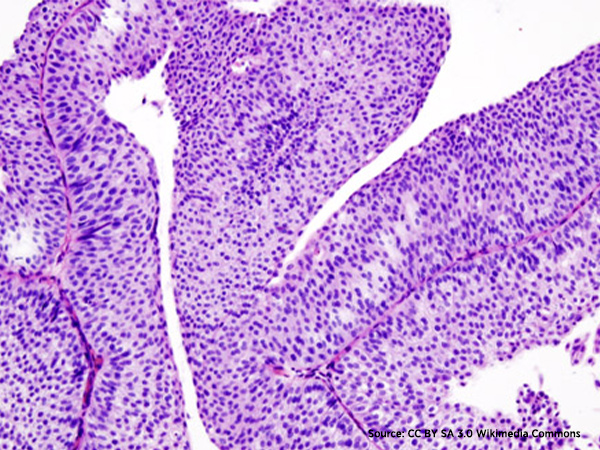

Bladder cancer is the sixth most commonly diagnosed cancer in the United States, according to the National Cancer Institute. More than 90 percent of the 80,470 new cases of bladder cancer expected to be diagnosed in the United States in 2019 will be classed as urothelial carcinomas because they will arise in cells that comprise the transitional cell urothelium that lines the bladder.